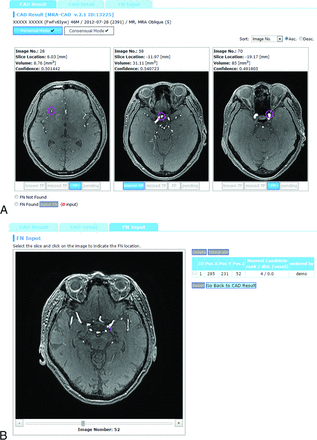

The CAD software used in this study was developed by our team. The details of the algorithm are published elsewhere.19 Briefly, after a lesion candidate detection based on curvatures20 and Hessian eigenvalues,21 a classifier ensemble trained by the boosting algorithm22 was used to determine the likelihood of an aneurysm on the basis of 63 feature values of the candidates, such as statistics of voxel values, curvatures, and features derived from Hessian eigenvalues. This software was installed as a plug-in for a Web-based CAD server developed by Nomura et al23 (Fig 2).

Example of CAD results displayed in the CAD server. A, Lesion classification interface. The top 3 lesion candidates are displayed, each of which has toggle buttons to select “known TP,” “missed TP,” “FP,” or “pending.” B, False-negative input interface. Radiologists recorded the locations of an aneurysm by a mouse click if it was not presented by the CAD system.

A radiologist categorized each lesion candidate as either a “known true-positive (TP),” a “missed TP,” a “false-positive (FP)”, or “pending.” Definitions were as follows: “known TP,” a true aneurysm that the radiologist had already recognized before seeing the CAD results; “missed TP,” a lesion that he or she overlooked before seeing the CAD results; and “FP,” a false-positive candidate (ie, not an aneurysm). The “pending” selection in the final diagnosis indicated that the 2 radiologists did not reach a positive consensus, mainly because the lesion was too small. Such subjects were not referred to experts for further evaluation; thus, we did not include such pending selections as positive aneurysms. If a lesion detected by the radiologist was not included in the 3 candidates displayed by the CAD system, the radiologist manually recorded the coordinates of the aneurysm by a mouse click (Fig 2B). Thus, by combining all these data, the server collected the following items: 1) all the locations of aneurysms determined by consensus, 2) whether each radiologist successfully detected the lesion before reviewing the CAD results, and 3) whether each positive lesion was successfully included in the CAD results as one of the top 3 candidates. Additionally, the median time for reviewing CAD results and giving feedback was determined by using the server log for the last 2 months of the data-acquisition period, by which time the radiologists were well-accustomed to the system.